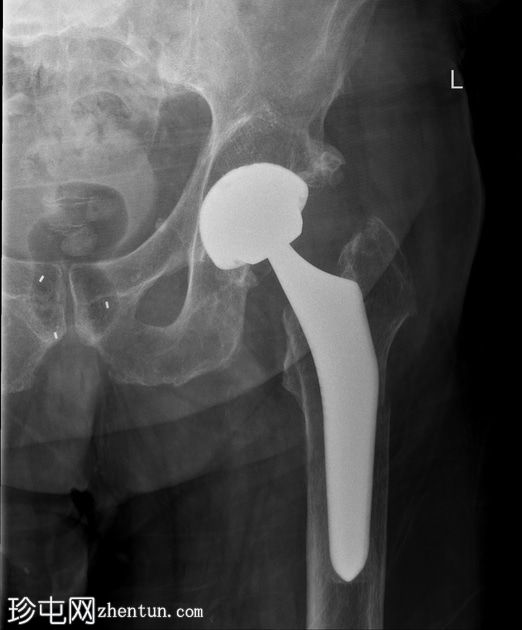

X光片

正面

可见左髋关节假体。左侧股骨近端存在轻微移位的假体周围骨折。

初次X光片和后续CT扫描均可见左股骨假体周围骨折。温哥华分类系统是目前最广泛使用的髋关节假体周围骨折分类系统。本例患者为温哥华B2型骨折。

患者随后接受了手术固定和翻修关节置换术。